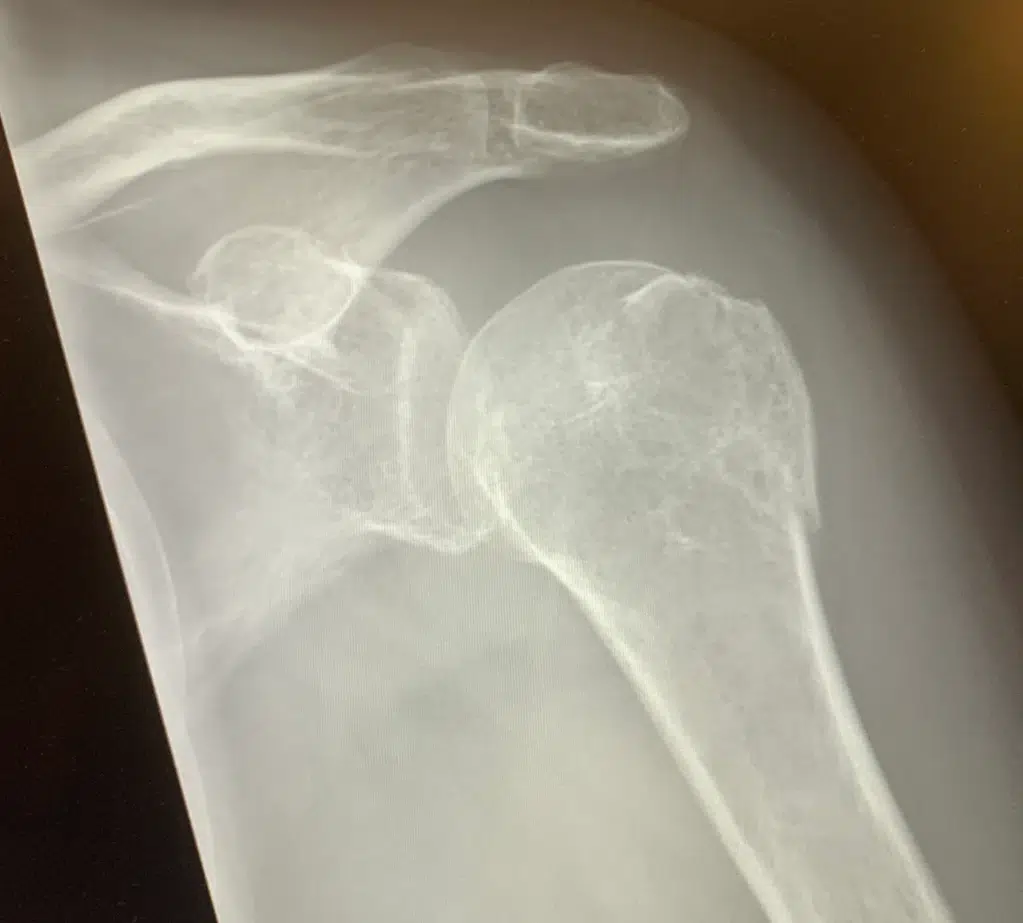

På Hvidovre har kirurgerne et genialt samarbejde med Osteoporoseenheden: Når man har pådraget sig et brud, og lægerne synes, man er blevet halvgammel, går der automatisk besked fra kirurgerne til Osteoporoseenheden, og når bruddet bør være vokset solidt sammen, får man indkaldelse til en såkaldt DEXA-scanning.

Jeg faldt i juli og er nu vokset ret grundigt sammen, så jeg var nede at blive scannet i morges.

Jeg har ikke osteoporose. Det er jeg utrolig glad for, for jeg havde været lidt nervøs. Det er da mystisk at falde over sine egne ben og pådrage sig to brud. Men alt er i orden og alle værdier er fuldkommen normale for en kvinde på 62 år. Jeg bør tage nogle kalktabletter, men det er da også det hele.

Jeg fik en kopi af alle billederne med hjem, for dem vil egen læge jo nok gerne se. Hun forklarede en masse om forskellige scores og tegnede og fortalte. Alle værdier ligger minimum på 98 pct., og det er meget fint.